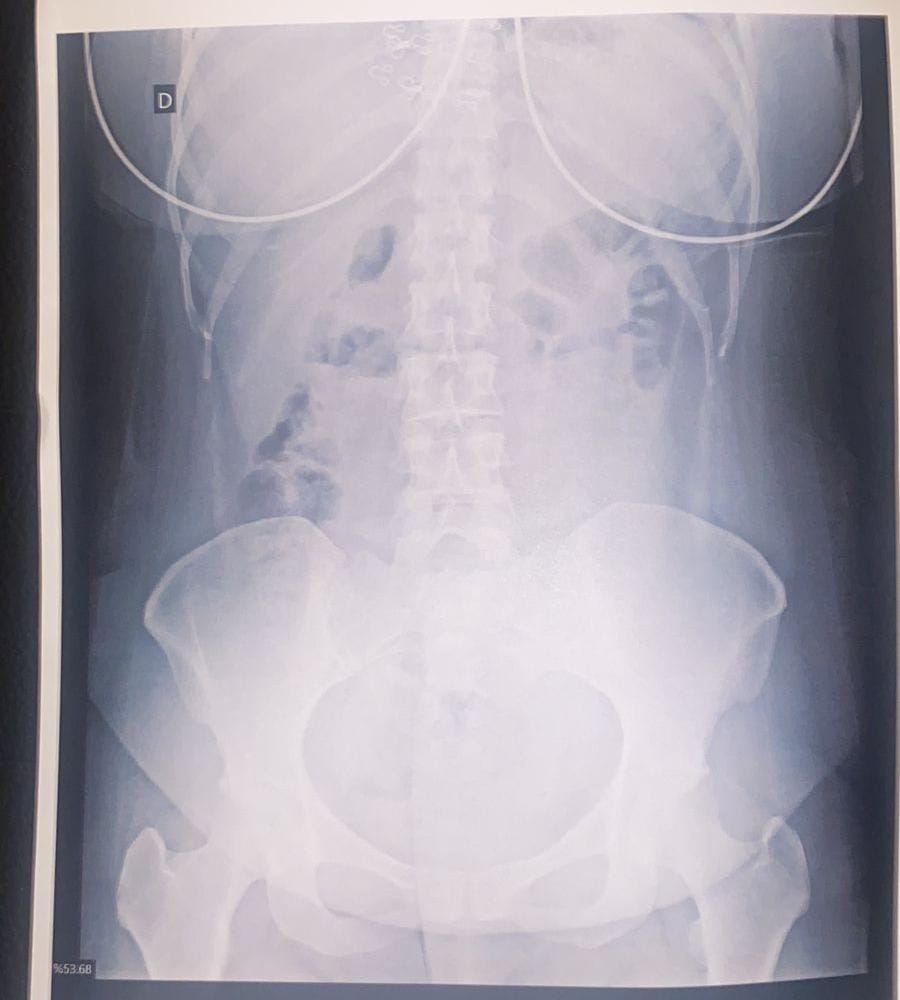

O suspeito, também, declarou que havia ingerido algumas das cápsulas e foi levado à Santa Casa de Corumbá. Ele foi submetido a um exame de Raio-X, que constatou aproximadamente 30 cápsulas ingeridas. No total, foram identificadas 95 cápsulas de droga sob porte do casal.